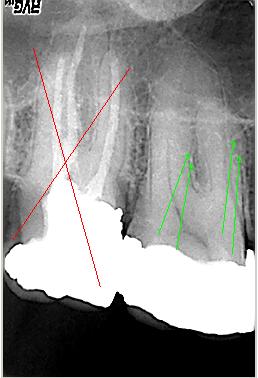

Bearbeitetes Röntgenbild

Bearbeitetes Röntgenbild mit Hinweis auf mögliche zusätzliche Kanalsysteme MB2 und DB2 Zahn 17 ist nicht erhaltungsfähig

Klinische Situation

Entsprechende klinische Situation mit den zunächst dargestellten Kanalsystemen P,MB1 und DB1(grüne Pfeile) sowie Kennzeichnung der später aufbereiteten MB2 und DB2 (rote Pfeile)